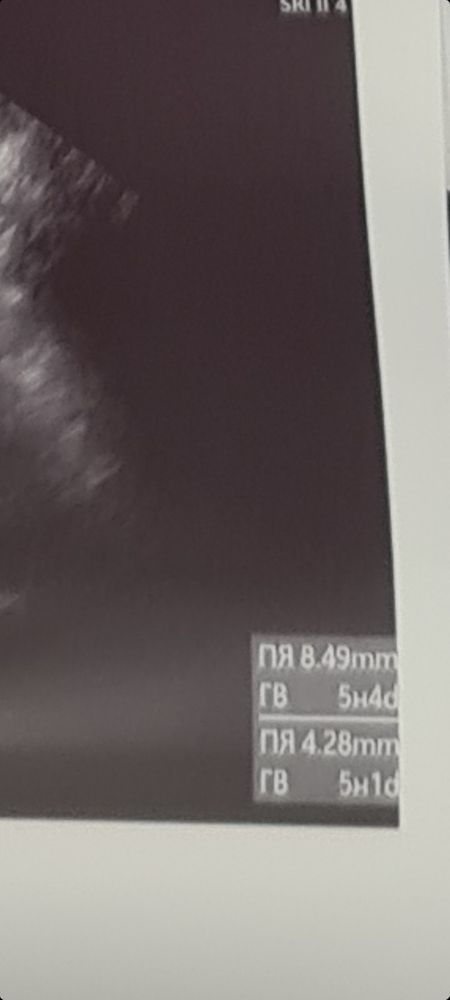

5 и 3 была. Акушерских. Увидели ПЯ, ЖМ И ЖТ в яичнике.

я хотела на хгч 1000 пойти, заработалась, сдала-2350, на след день пошла, увидели пя, 6 мм, жм 2мм. Думаю на полутора можно смело идти

Первый раз в 4 ак.недели было ПЯ 4 мм - сын, второй раз в 5,2 акк.недель всего 3 мм - ЗБ.